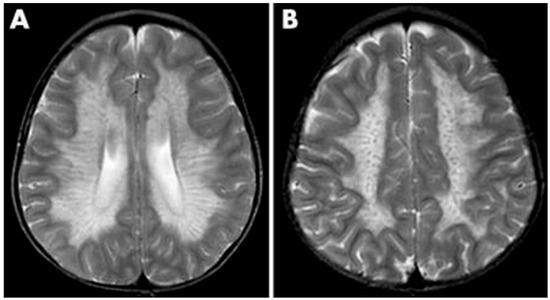

- Groeschel, S.; Kehrer, C.; Engel, C.; I Dali, C.; Bley, A.; Steinfeld, R.; Grodd, W.; Krägeloh-Mann, I. Metachromatic leukodystrophy: Natural course of cerebral MRI changes in relation to clinical course. J. Inherit. Metab. Dis. 2011, 34, 1095–1102. [Google Scholar] [CrossRef]

- Schoenmakers, D.H.; Beerepoot, S.; Krägeloh-Mann, I.; Elgün, S.; Bender, B.; van der Knaap, M.S.; Wolf, N.I.; Groeschel, S. Recognizing early MRI signs (or their absence) is crucial in diagnosing metachromatic leukodystrophy. Ann. Clin. Transl. Neurol. 2022, 9, 1999–2009. [Google Scholar] [CrossRef]

- Martin, A.; Sevin, C.; Lazarus, C.; Bellesme, C.; Aubourg, P.; Adamsbaum, C. Toward a better understanding of brain lesions during metachromatic leukodystrophy evolution. AJNR. Am. J. Neuroradiol. 2012, 33, 1731–1739. [Google Scholar] [CrossRef] [PubMed]